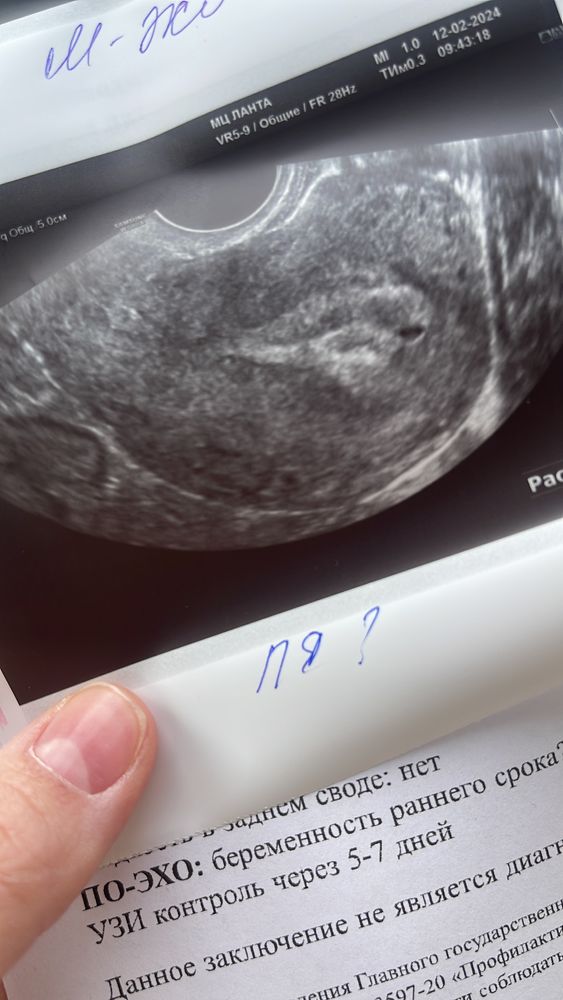

Изображение YuliiaBoiko, а я сегодня ходила, в клинике была с ребенком у педиатра, и решила проверить маточная ли беременность, окошко как раз было у узиста. Она нашла точку в матке, сказала что с уверенностью сказать не может, так как нет желчного мешочка и имбриона пока не видно. Но желтое тело есть, овуляция с левого яичника, эндометрий хороший если Б. Вообщем сказала не раньше чем через 7 дней приходить. Я решила подождать еще недели 2-3 чтобы уже сразу и сердечко послушать (акушерских 7-8 будет). А то после первых родов уже была замершая, там я каждую неделю бегала, так как переживала.. Как вспомню что каждое узи (на 4/5/6/7 недели) никакое инфо не приносило: ждите, рано видимо еще, давайте через дней 7… и так до 8 недель. Больше нервов испытала в ожидании когда услышат, спать не могла((( В этот раз хочу сразу к 8 пойти во второй раз.. и представлять до этого что все хорошо ☺️))) напишите потом что у вас увидели)

YuliiaBoiko, так как у нас сроки и ХГЧ примерно одинаковые, я бы Вам рекомендовала попозже узи сделать, судя по моиму снимку 😂А то здесь спорят на форуме, вредно узи на таких сроках или нет.. уже начинаю задумываться, может действительно вредно 🙈 Я выписалась с 20.02 числа 😅Буду дольше ждать

Изображение

Камила, привет, да! ПЯ 3 мм. Срок 3 недели. След узи 5.03.